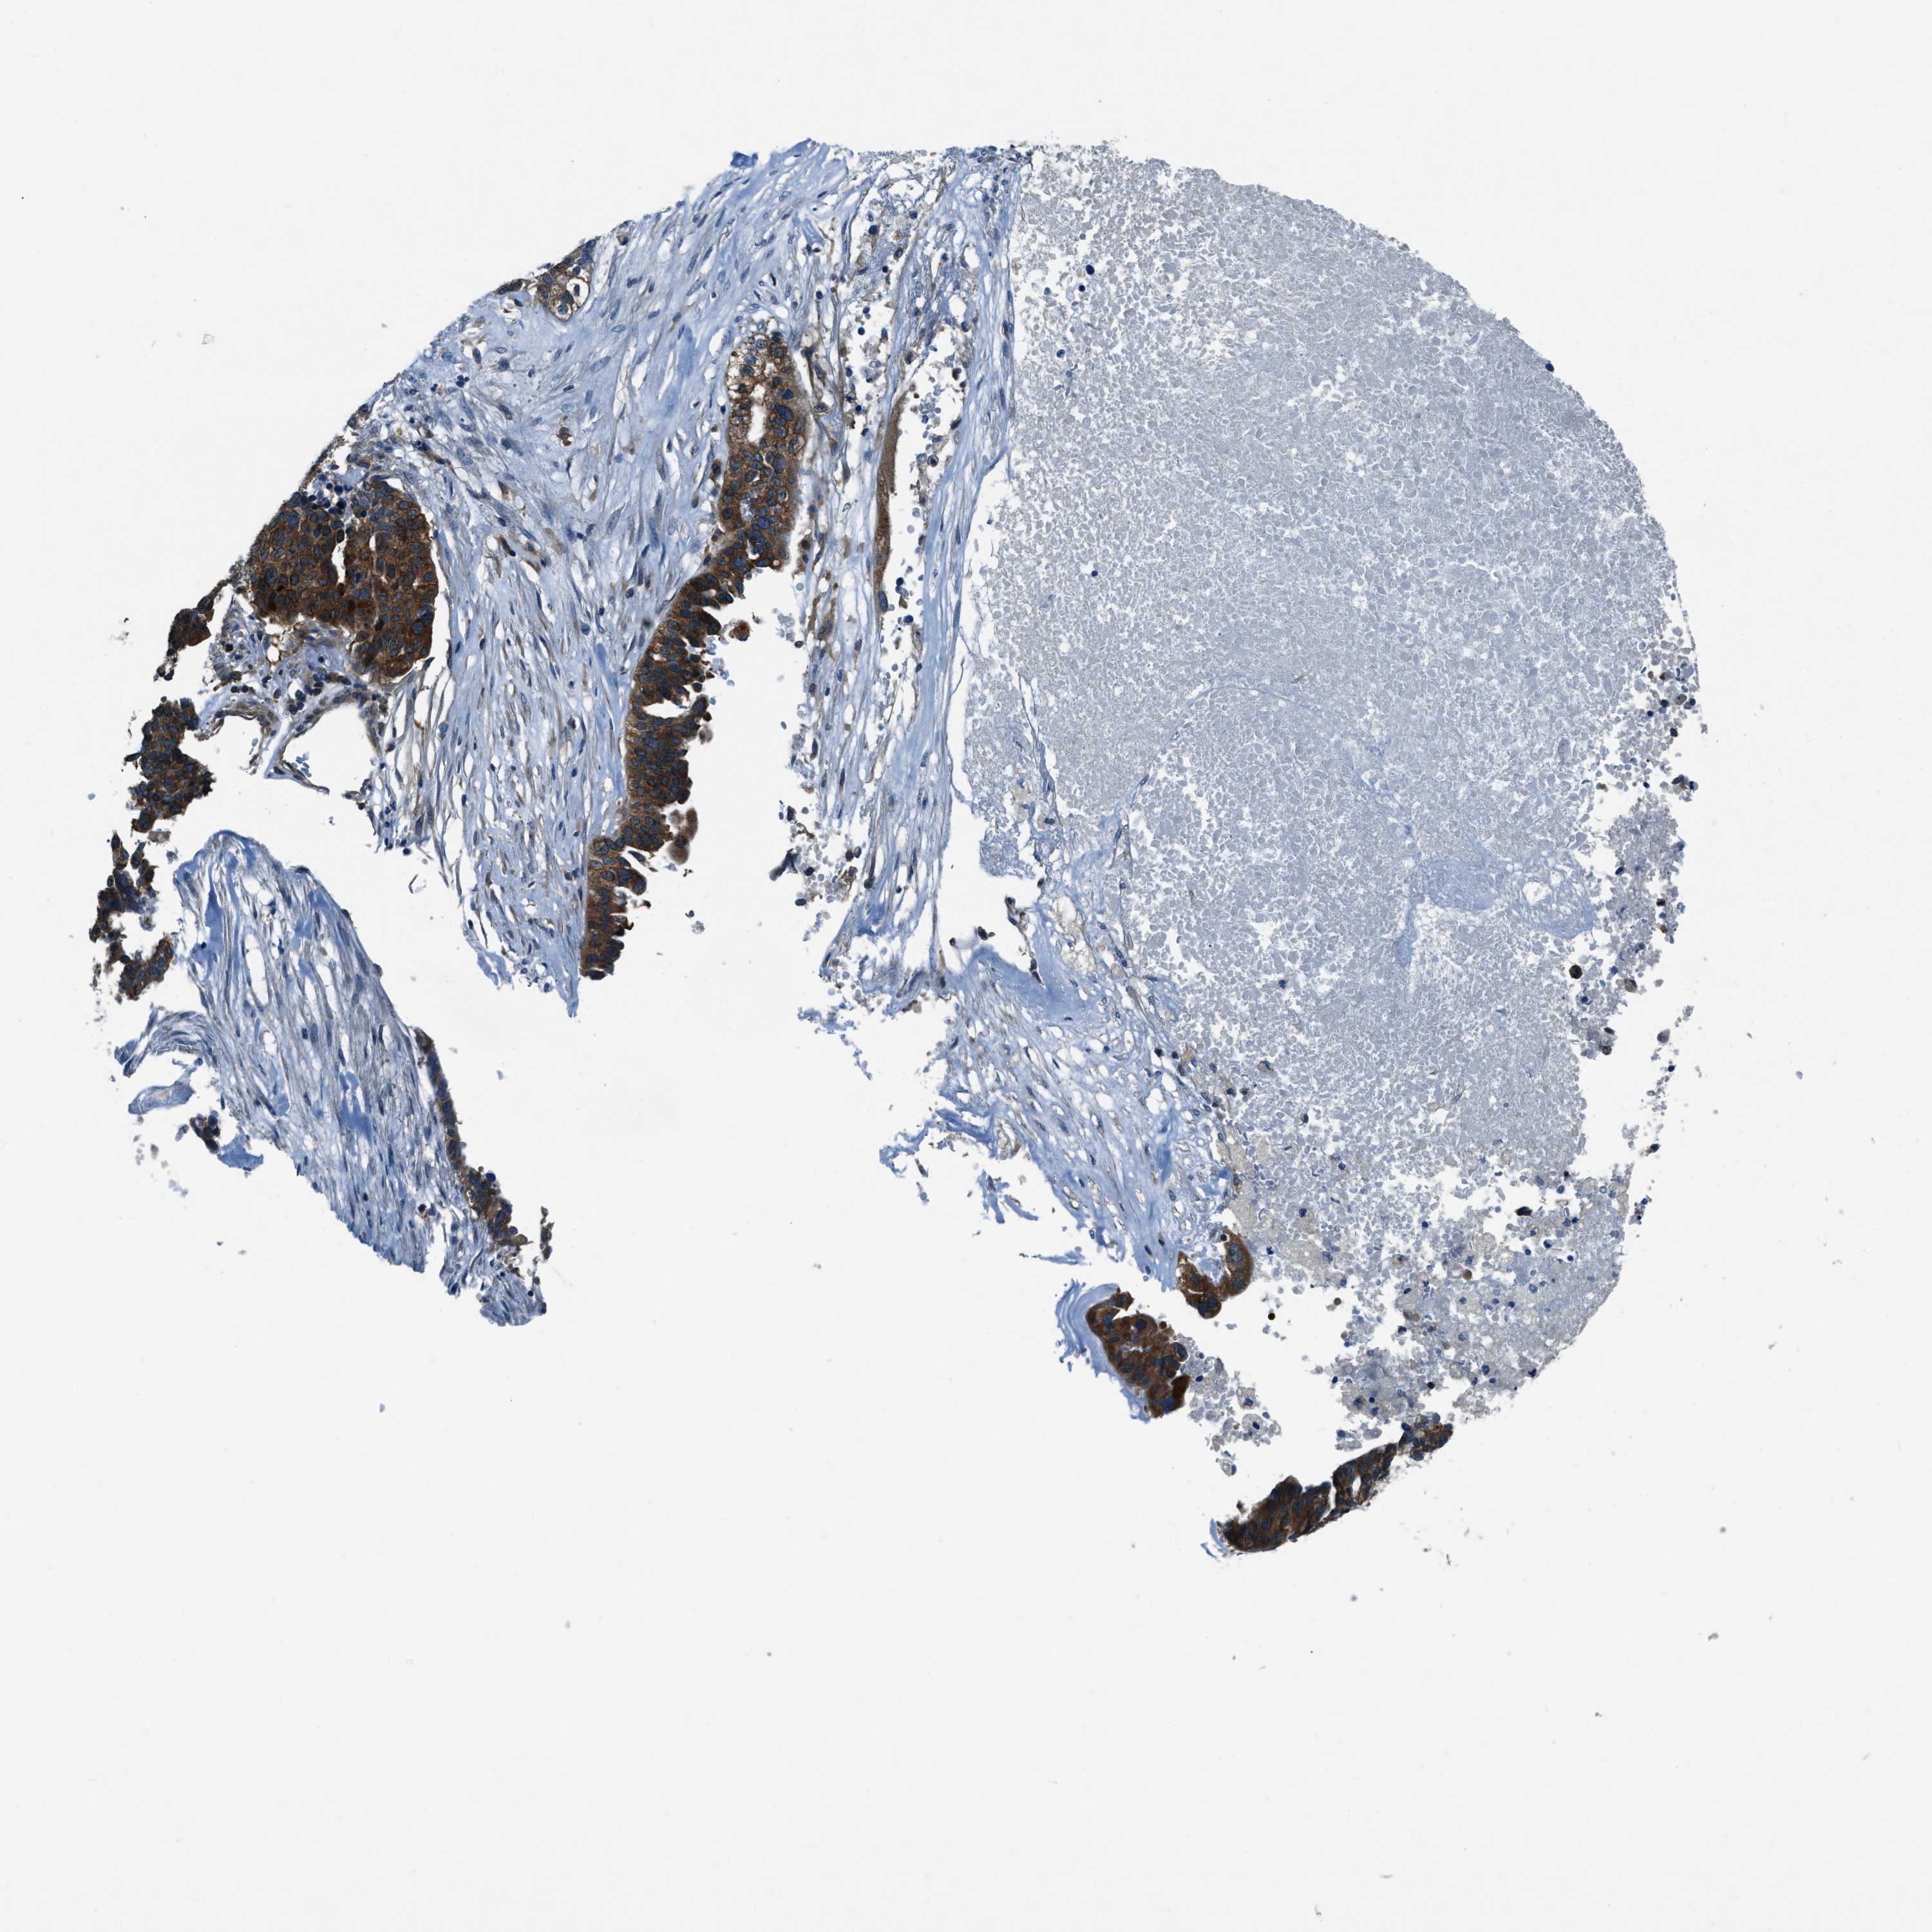

OVARIAN CANCER - Protein expressioni

A mouse-over function shows sample information and annotation data. Click on an image to view it in a full screen mode. Samples can be filtered based on level of antibody staining by selecting one or several of the following categories: high, medium, low and not detected. The assay and annotation is described here.

Note that samples used for immunohistochemistry by the Human Protein Atlas do not correspond to samples in the TCGA dataset.

Antibody stainingi

Antibody staining in the annotated cell types in the current human tissue is reported as not detected, low, medium, or high, based on conventional immunohistochemistry profiling in selected tissues. This score is based on the combination of the staining intensity and fraction of stained cells.

Each image is clickable and will lead to virtual microscopy that enables deeper exploration of all samples and also displays staining intensity scores, fraction scores and subcellular localization as well as patient and tissue information for each sample.

Antibody HPA016649

Antibody HPA018152

Cystadenocarcinoma, serous, NOS

Carcinoma, endometroid

Cystadenocarcinoma, mucinous, NOS

Carcinoma, NOS